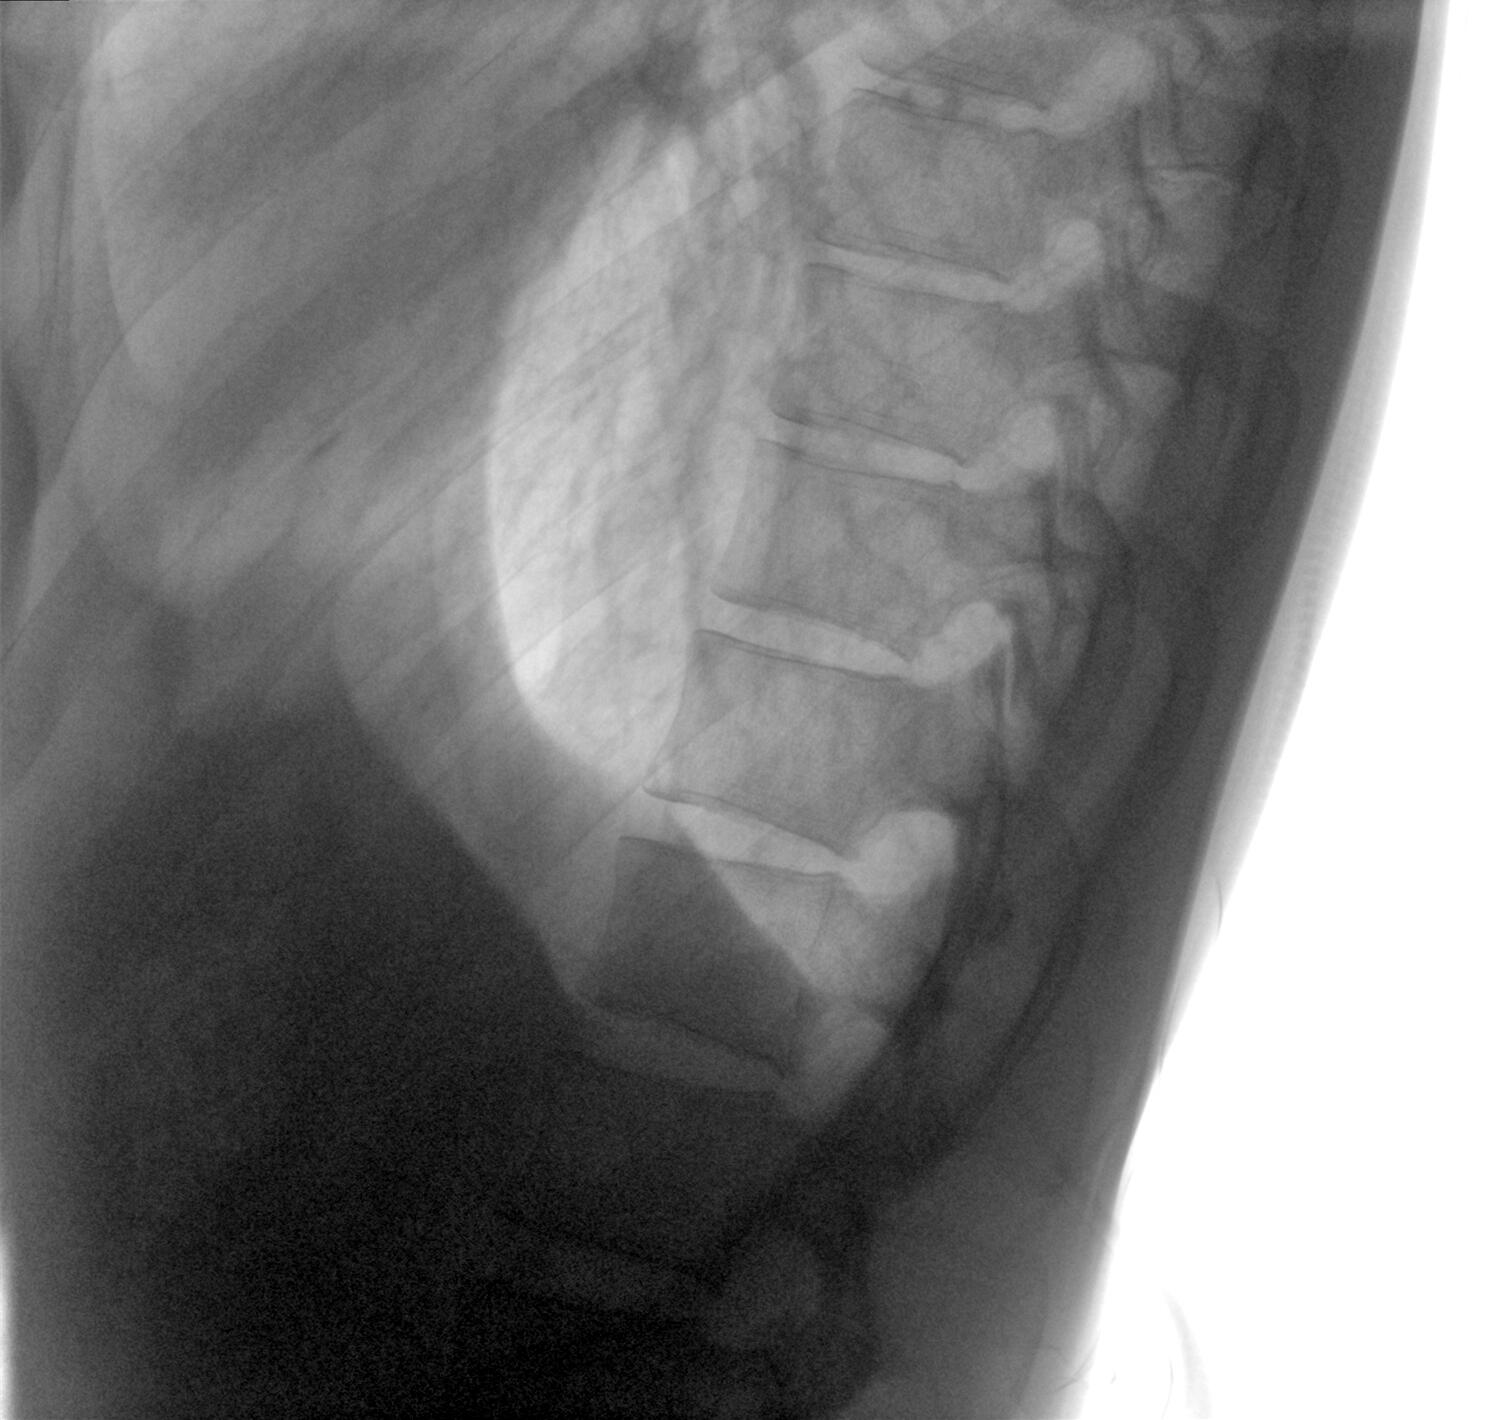

Clinical picture

臨床圖片